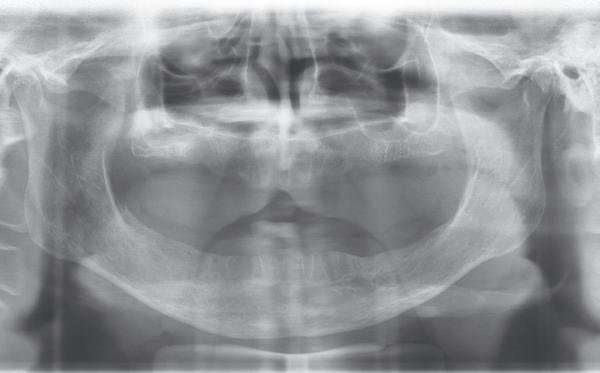

Een patiënt die conventioneel tandheelkundig vrijwel volledig is uitbehandeld, stelt de behandelaar voor complexe keuzes. In dit artikel wordt aan de hand van een uitgebreide casus beschreven hoe diagnostiek, prognosebepaling en interdisciplinair overleg leiden tot een voorspelbaar implantologisch behandeltraject. De casus illustreert hoe een ogenschijnlijk onsamenhangende restauratieve voorgeschiedenis kan uitmonden in een doordacht en succesvol full-arch implantaatgedragen rehabilitatieplan.

Op maandagochtend halfnegen dient zich in mijn agenda een nieuwe patiënt aan, mevrouw G. Ik heb haar nooit eerder gezien en een verwijzend tandarts, stuurt haar in met de vraag of ik met implantaten het eerste kwadrant wil restaureren aangezien daar de brug is losgekomen. Eerder heeft mevrouw G. een uitgebreide informed consent ontvangen met een gezondheidsvragenlijst. Er is verder intensief contact geweest met de verwijzer die ook enkele gemaakte röntgenfoto’s heeft gemaild. Tijdens het eerste onderzoek blijkt dat ze zich goed heeft ingelezen in alle informatie die haar per mail is toegestuurd. De patiënt is 65 jaar oud, spreekt moeilijk Nederlands, echter in het Engels kan ze zich goed verstaanbaar maken. Bij navraag blijkt ze in verschillende landen te hebben gewoond in verband met de werkzaamheden van haar man. Ze is van een economisch hogere sociale klasse en woont nu sinds een jaar of vijf in Nederland. Ze is gezond en slikt geen medicijnen, behalve pijnstillers tegen de pijn in haar gebit.

Er worden lichtfoto’s gemaakt van het gebit waarop blijkt dat enkel een aantal incisieven in boven- en onderkaak onbehandeld zijn (zie lichtfoto’s bij intake). De residentie lijkt vrijwel geheel gekroond en/ of overbrugd. Er is sprake van gedateerd kroon- en brugwerk waarbij kroonranden met de jaren bloot zijn komen te liggen en er is sprake van secondaire cariës. Daarnaast stel ik een fors verlies van verticale hoogte van de aanwezige processus in alle vier de kwadranten vast. Is hier sprake geweest van een verleden met ernstige parodontitis?

1. Gedateerd kroon- en brugwerk; fors aanhechtingsverlies zijdelingse elementen.

2. Ernstige parodontale afbraak verspreid aanwezig; (sec.)cariës

onder de kronen; grote apicale radiolucentie 16.

3. Paro status bij intake

4. Op basis van de OPG is niet nader te bepalen wat de breedte is van

Op basis van de eerste indruk die ik krijg tijdens het globale klinische onderzoek, wordt een orthopantamogram (zie OPT bij intake) gemaakt. Samen met de meegestuurde röntgenopnames (zie solo’s) wordt eenvoudig vastgesteld dat er sprake is van ernstig botverlies, bijvoorbeeld bij de 16, 17 en de 18 tot 100% verlies aan alveolair bot. De 16 vertoont daarnaast een grote peri-apicale laesie. In het eerste kwadrant lijkt daarom alleen de 12 een goede prognose te hebben. De 12 vormt samen met de 16 een vierdelige brug en deze constructie lijkt dus verloren. Overigens vermoed ik dat de 12 eigenlijk een cuspidaat is en ontbreekt de 12 (agenesie). Daarnaast worden sterk verdiepte ontstoken pockets geconstateerd bij de 16, 17 tot 12 mm en zijn de elementen sterk verhoogd mobiel. De 11 lijkt als enige element van de gehele dentitie niet te zijn behandeld.

7. OPT na abutmentchirurgie 6 maanden later. De integratie van de implantaten met de botopbouw & sinusliften verloopt voorspoedig.